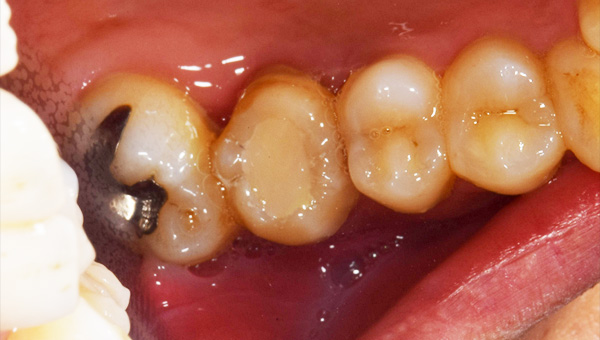

初診時のパノラマ

説明:

初診時のパノラマです。左下の一番奥の歯が虫歯になっているのがわかります。